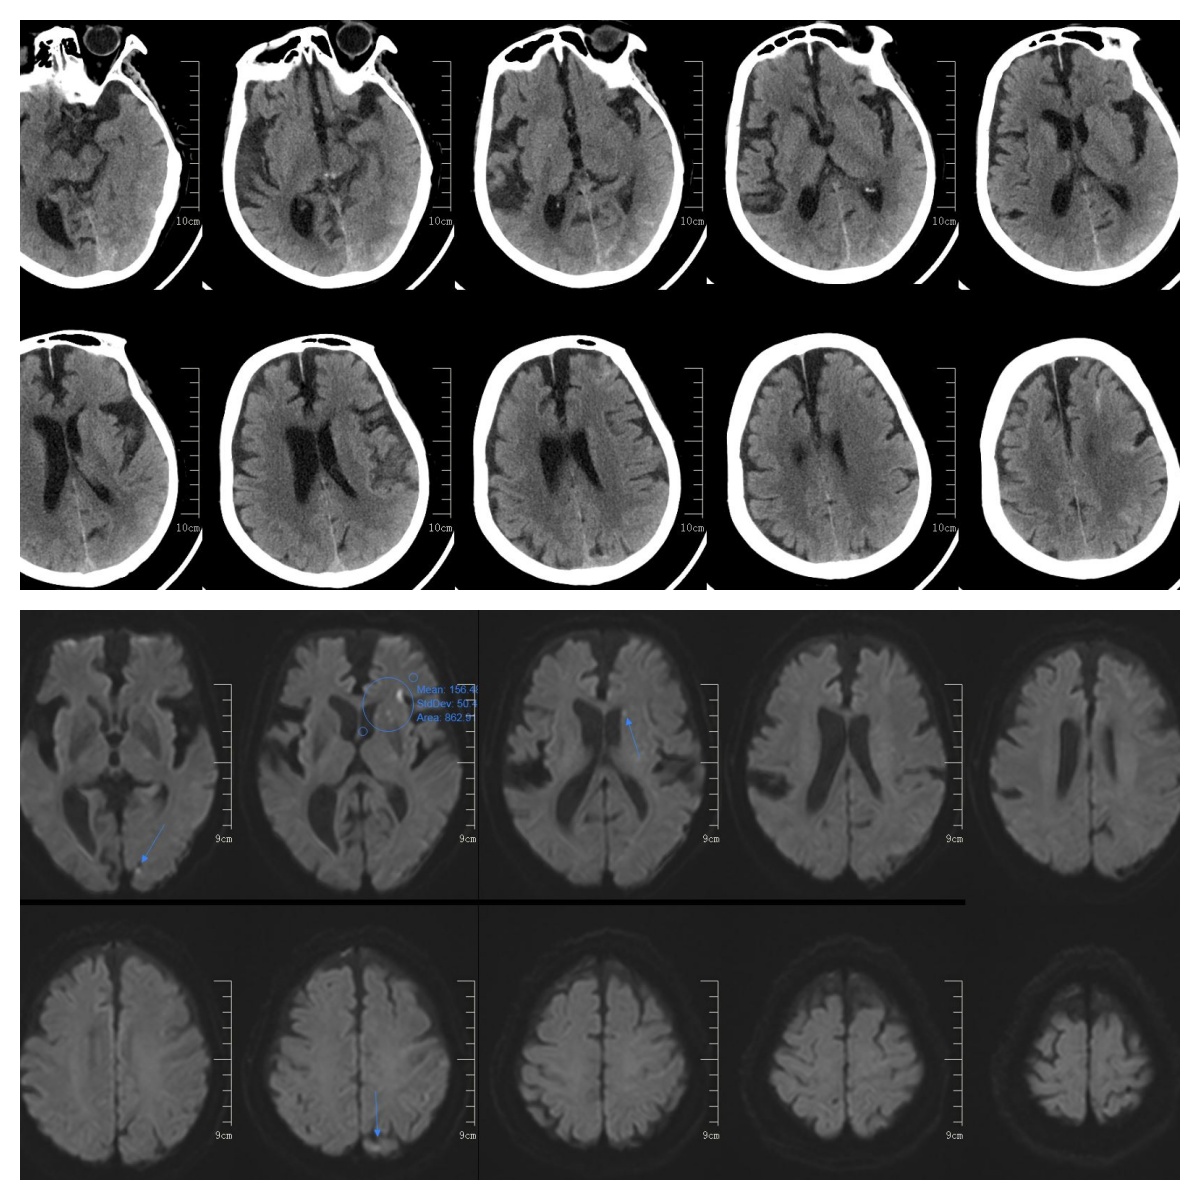

术后患者顺利苏醒麻醉,右侧肢体功能机语言功能明显改善,复查头颅CT,提示有少量蛛网膜下腔出血,磁共振提示左侧大脑半球多发腔隙性脑梗死。

患者术后蛛网膜下腔有少量出血,动态复查出血无明显增加,未见大面积梗死灶,予患者继续使用抗血小板药物治疗,目前处康复中。